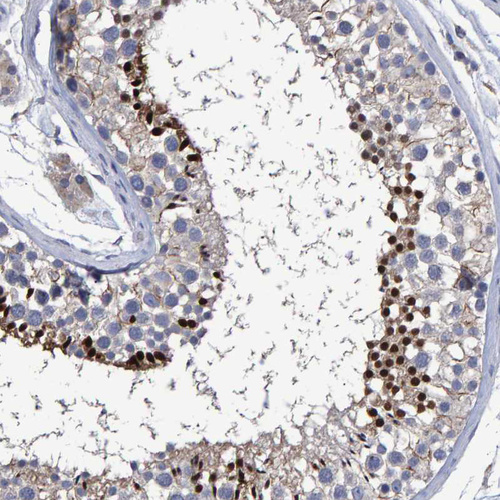

Immunohistochemistry analysis in human bone marrow and cerebral cortex tissues using HPA019572 antibody. Corresponding HEMGN RNA-seq data are presented for the same tissues.